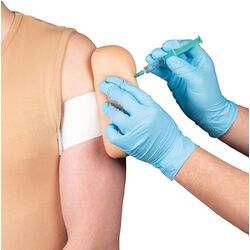

Pritvirtinamas vakcinacijos treniruoklis – Erler Zimmer

€136.00 Į krepšelį -